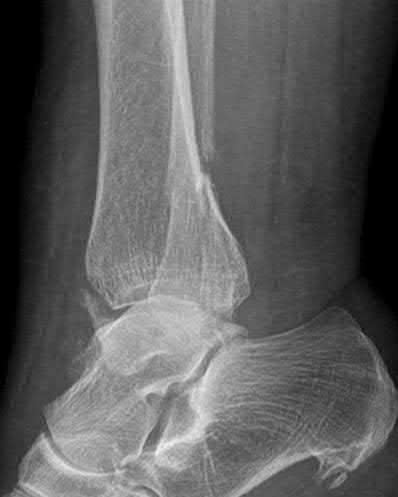

Question 2

A 28-year-old male sustains a severe hyper-dorsiflexion injury to his ankle in a motor vehicle accident, resulting in a Hawkins Type III talar neck fracture. Which of the following arteries provides the predominant blood supply to the body of the talus, placing it at significant risk for avascular necrosis in this injury?

Explanation

The artery of the tarsal canal, which is a branch of the posterior tibial artery, provides the dominant blood supply to the talar body. In a Hawkins Type III fracture (talar neck fracture with subtalar and tibiotalar dislocation), the blood supply from the artery of the tarsal canal, the artery of the sinus tarsi, and capsular vessels are disrupted, leading to an avascular necrosis (AVN) rate approaching 100%.